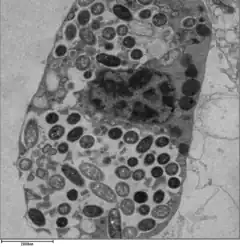

.jpg)

L. pneumophila is able to invade and replicate within human alveolar macrophages. Internalization of the bacteria appears to occur through phagocytosis or coiling phagocytosis and is reliant on Dot/Icm type 4B secretion system (T4BSS). Once internalized, the Dot/Icm system begins secreting bacterial effector proteins that recruit host factors to the Legionella containing vacuole (LCV). This process prevents the LCV from fusing with the lysosomes that would otherwise degrade the bacteria. Vesicles of the host cell's rough endoplasmic reticulum are attracted to the LCV, and these vacuoles supply the LCV with necessary lipids and proteins.[13] LCV membrane integrity requires a steady supply of host lipids, such as cellular cholesterol and the cis-monounsaturated fatty acid, palmitoleic acid.[31][32] L. pneumophila replication occurs within the LCV. Once nutrients are depleted, the bacteria gain flagella and cytoxicity. To exit the host cell, L. pneumophila lyses the LCV and resides in the cytoplasm. In the cytoplasm, L. pneumophila inhibit organelle and plasma membrane function and structure which ultimately leads to osmotic lysis of the host cell.[33]

Legionella-containing vacuole

For Legionella to survive within macrophages and protozoa, it must create a specialized compartment known as the Legionella-containing vacuole (LCV).[37] Through the action of the Dot/Icm secretion system, the bacteria are able to prevent degradation by the normal endosomal trafficking pathway and instead replicate. Shortly after internalization, the bacteria specifically recruit endoplasmic reticulum-derived vesicles and mitochondria to the LCV while preventing the recruitment of endosomal markers such as Rab5a and Rab7a. Formation and maintenance of the vacuoles are crucial for pathogenesis; bacteria lacking the Dot/Icm secretion system are not pathogenic and cannot replicate within cells, while deletion of the Dot/Icm effector SdhA results in destabilization of the vacuolar membrane and no bacterial replication.[38][39]